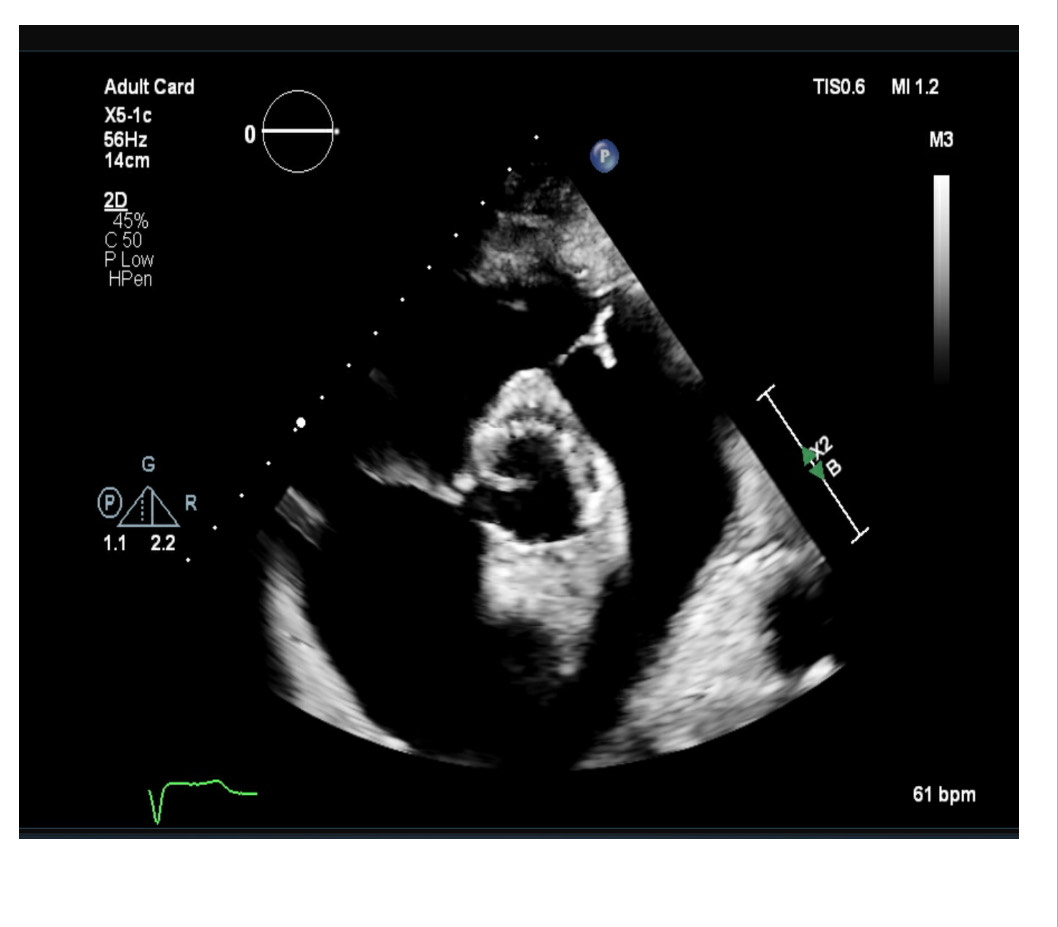

Post-TAVI aortography confirmed proper valve positioning with only a trivial paravalvular leak (PVL). The access sites were successfully closed using ProGlide and Angio-Seal devices. A total of 50 cc of Gadobutrol was used. Pre-discharge transthoracic echocardiography (TTE) confirmed good transcatheter heart valve (THV) positioning, no PVL, and a peak gradient of 6 mmHg. Renal function tests performed one week post-procedure showed no deterioration, with a creatinine level of 156 µmol/L.

Post-TAVI aortography confirmed proper valve positioning with only a trivial paravalvular leak (PVL). The access sites were successfully closed using ProGlide and Angio-Seal devices. A total of 50 cc of Gadobutrol was used. Pre-discharge transthoracic echocardiography (TTE) confirmed good transcatheter heart valve (THV) positioning, no PVL, and a peak gradient of 6 mmHg. Renal function tests performed one week post-procedure showed no deterioration, with a creatinine level of 156 µmol/L.